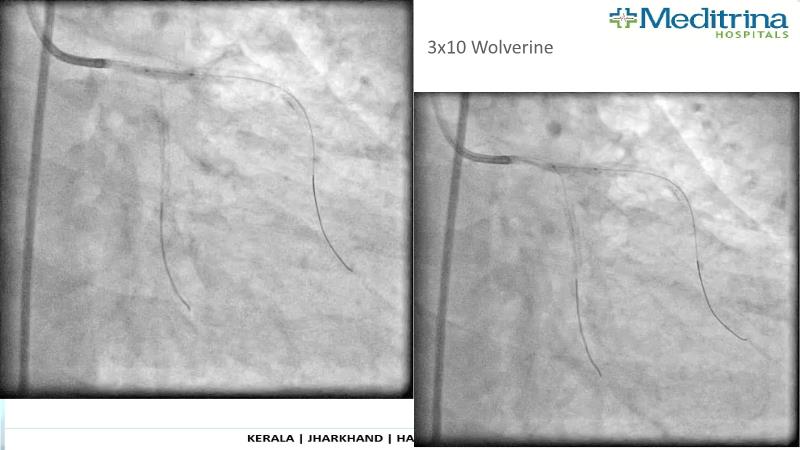

- To define the use of OCT in PCI of complex coronary lesions